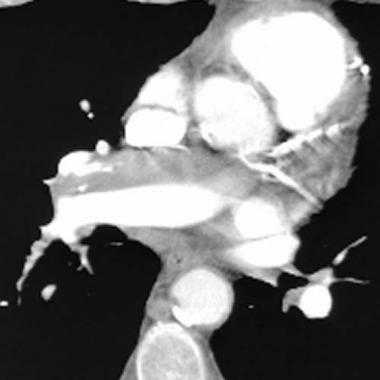

(б) При КТ с контрастным усилением в левой легочной артерии визуализируется экспансивный рост гиподенсного мягкотканного объемного образования. При биопсии была выявлена саркома легочной артерии. Следует отметить наличие послеоперационных изменений в левой половине грудной клетки. Саркомы легочной артерии могут полностью заполнять ее просвет и вызывать расширение сосуда, как в данном случае. (а) Пациент с персистирующим тромбом в правой легочной артерии после попытки лечения антикоагулянтами по поводу предполагаемой тромбоэмболии. При ФДГ-ПЭТ/КТ в области расположения предполагаемого тромба определяется интенсивный уровень поглощения ФДГ. При биопсии была выявлена саркома легочной артерии.